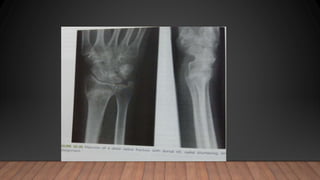

comminuted intraarticular fracture of the distal radius

Volar rim maintains relationship with the carpus and both

are displaced proximally (blue arrow)

Fracture of radial styloid process with loss of radial

inclination (yellow arrow)